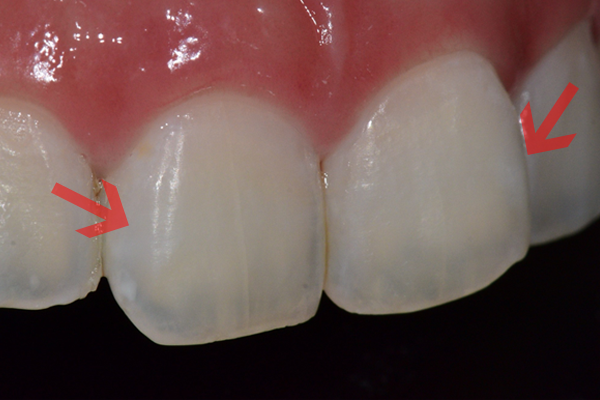

치아를 삭제하는 방법(기존의 레진, 라미네이트, 크라운 등)으로 치료하기 전

치아를 삭제하지 않고 레진을 치아에 침투시키는 원리로 치료합니다.

기존 재료를 사용함에 비해 치아 내부 투명도를 복원하기에 탁월하여 자연스러운 색과 질감으로 치아를 복원합니다.

치아 삭제가 필요하지 않는 것이 가장 큰 장점입니다.

치료 전